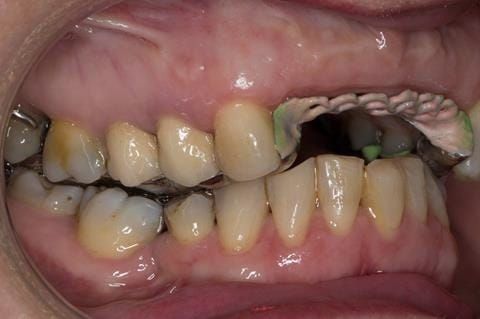

Provision of a maxillary cobalt chromium based partial denture/protective occlusal splint in a heavily restored dentition

- Other than the maxillary incisors the remaining dentition was in marginally better condition being moderately to heavily restored. Many will probably require replacement and restoration from time to time mainly from wear and tear owing to occlusal forces.

- Extract the upper 2-2 teeth and replace with an interim acrylic based partial denture. Reline the interim denture over 9 - 12 months, replacing with a definitive cobalt chromium based partial denture. The definitive denture would ideally be designed as an occlusal protective splint to reduce the the potential for mechanical wear and breakages of the moderately/heavily restored maxillary dentition. In addition, should further upper teeth require extraction they could be added on to the denture cobalt chromium framework - therefore a new prosthesis would not be required as future teeth are lost. This option would produce an excellent aesthetic outcome. This is the option the patient chose to have.

Following consultation and second discussion appointment the patient chose to have option 3 namely, a maxillary cobalt chromium based partial denture/protective occlusal splint. The clinical situation and treatment process is shown in detail below with photographs. The patient was successfully rehabilitated with this and her quality of life considerably improved. The clinical work was provided by Finlay and the technical work by Rowan.